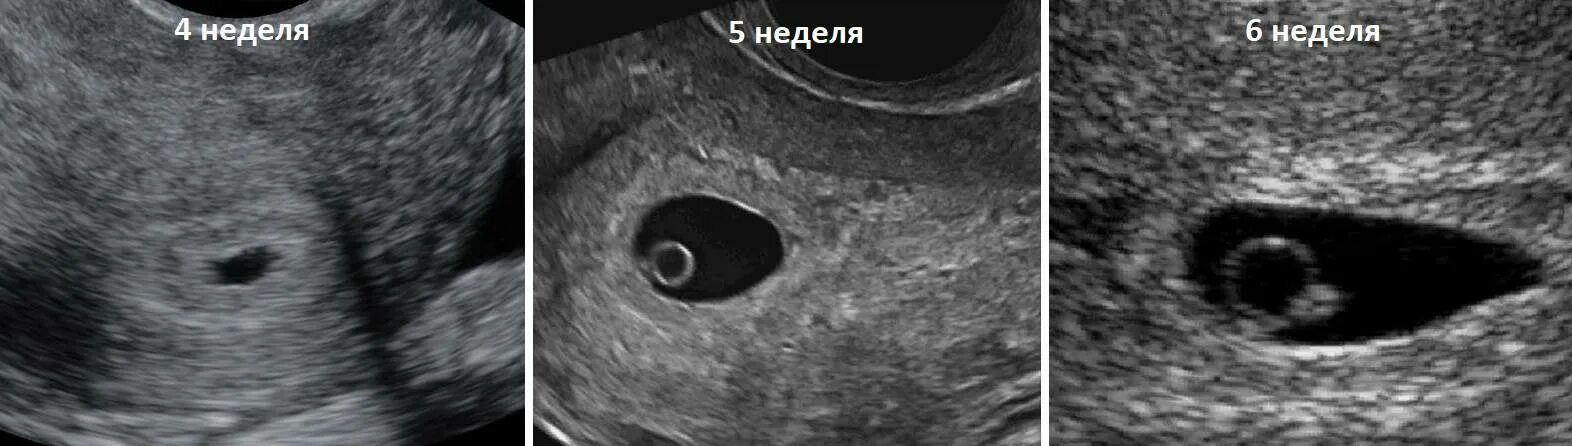

Как выглядит срока